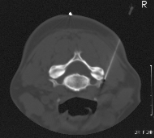

Die bisherige Therapie konnte keine stabile Ausheilung der Erkrankung bewirken. Aus diesem Grund ist die Durchführung einer Serie von zunächst 4-6 CT-gestützten Interventionen an der Wirbelsäule geplant. Mit der periradikulären Therapie bieten wir Ihnen ein modernes und erprobtes Verfahren zur Schmerztherapie im Wirbelsäulenbereich an. Dabei wird unter computertomo- graphischer Kontrolle eine dünne Nadel unter lokaler Betäubung bis unmittelbar an bzw. in den zu therapierenden Bereich vorgeschoben.

Die Computertomographie ist in der Lage, exakt Nerven, Blutgefäße und andere Körpergewebe darzustellen. Für die periradikuläre Therapie bedeutet dies erhöhte Sicherheit und die Gewährleistung einer hohen Präzision bei jeder Behandlung. Auch die zur Therapie eingesetzten Instrumente sind exakt im Bild zu erkennen und zu kontrollieren. Dadurch gelingt es, präzise Medikamente um den geschädigten Nerven bzw. in das Wirbelgelenk zu applizieren.